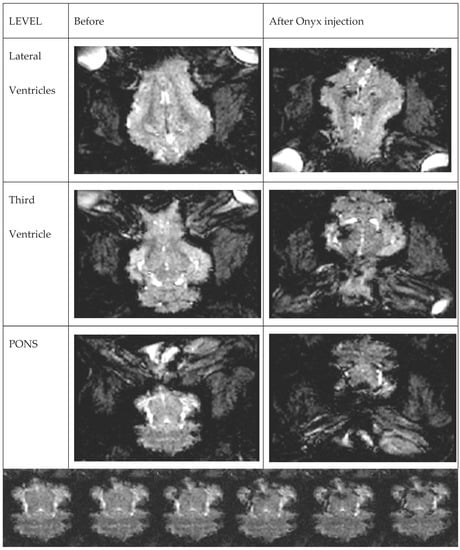

Onyx propagation was observed in real-time with initial ipsilateral RM filling followed by some main cerebral arteries and their branches distribution. The relatively bright signal within RM and the brain prior to Onyx injection provided a good background for the dark, low signal of the embolic agent spreading in rete mirabile and small brain arteries. (Supplementary Material Video S2/Figure 2).

Figure 2.

Real-time, dynamic EPI-GRE T2 scan of the whole brain volume during Onyx injection. Images on different levels before and after injection. The gradual filling is presented in Supplementary Material Video S2.

Supplementary Material Video S2: Real-time, dynamic EPI-GRE T2 scan of the whole brain volume during Onyx injection. Cine sequence of the Onyx propagation at the level of the pons. Dark liquid embolic agent is gradually filling small arteries around the pons.